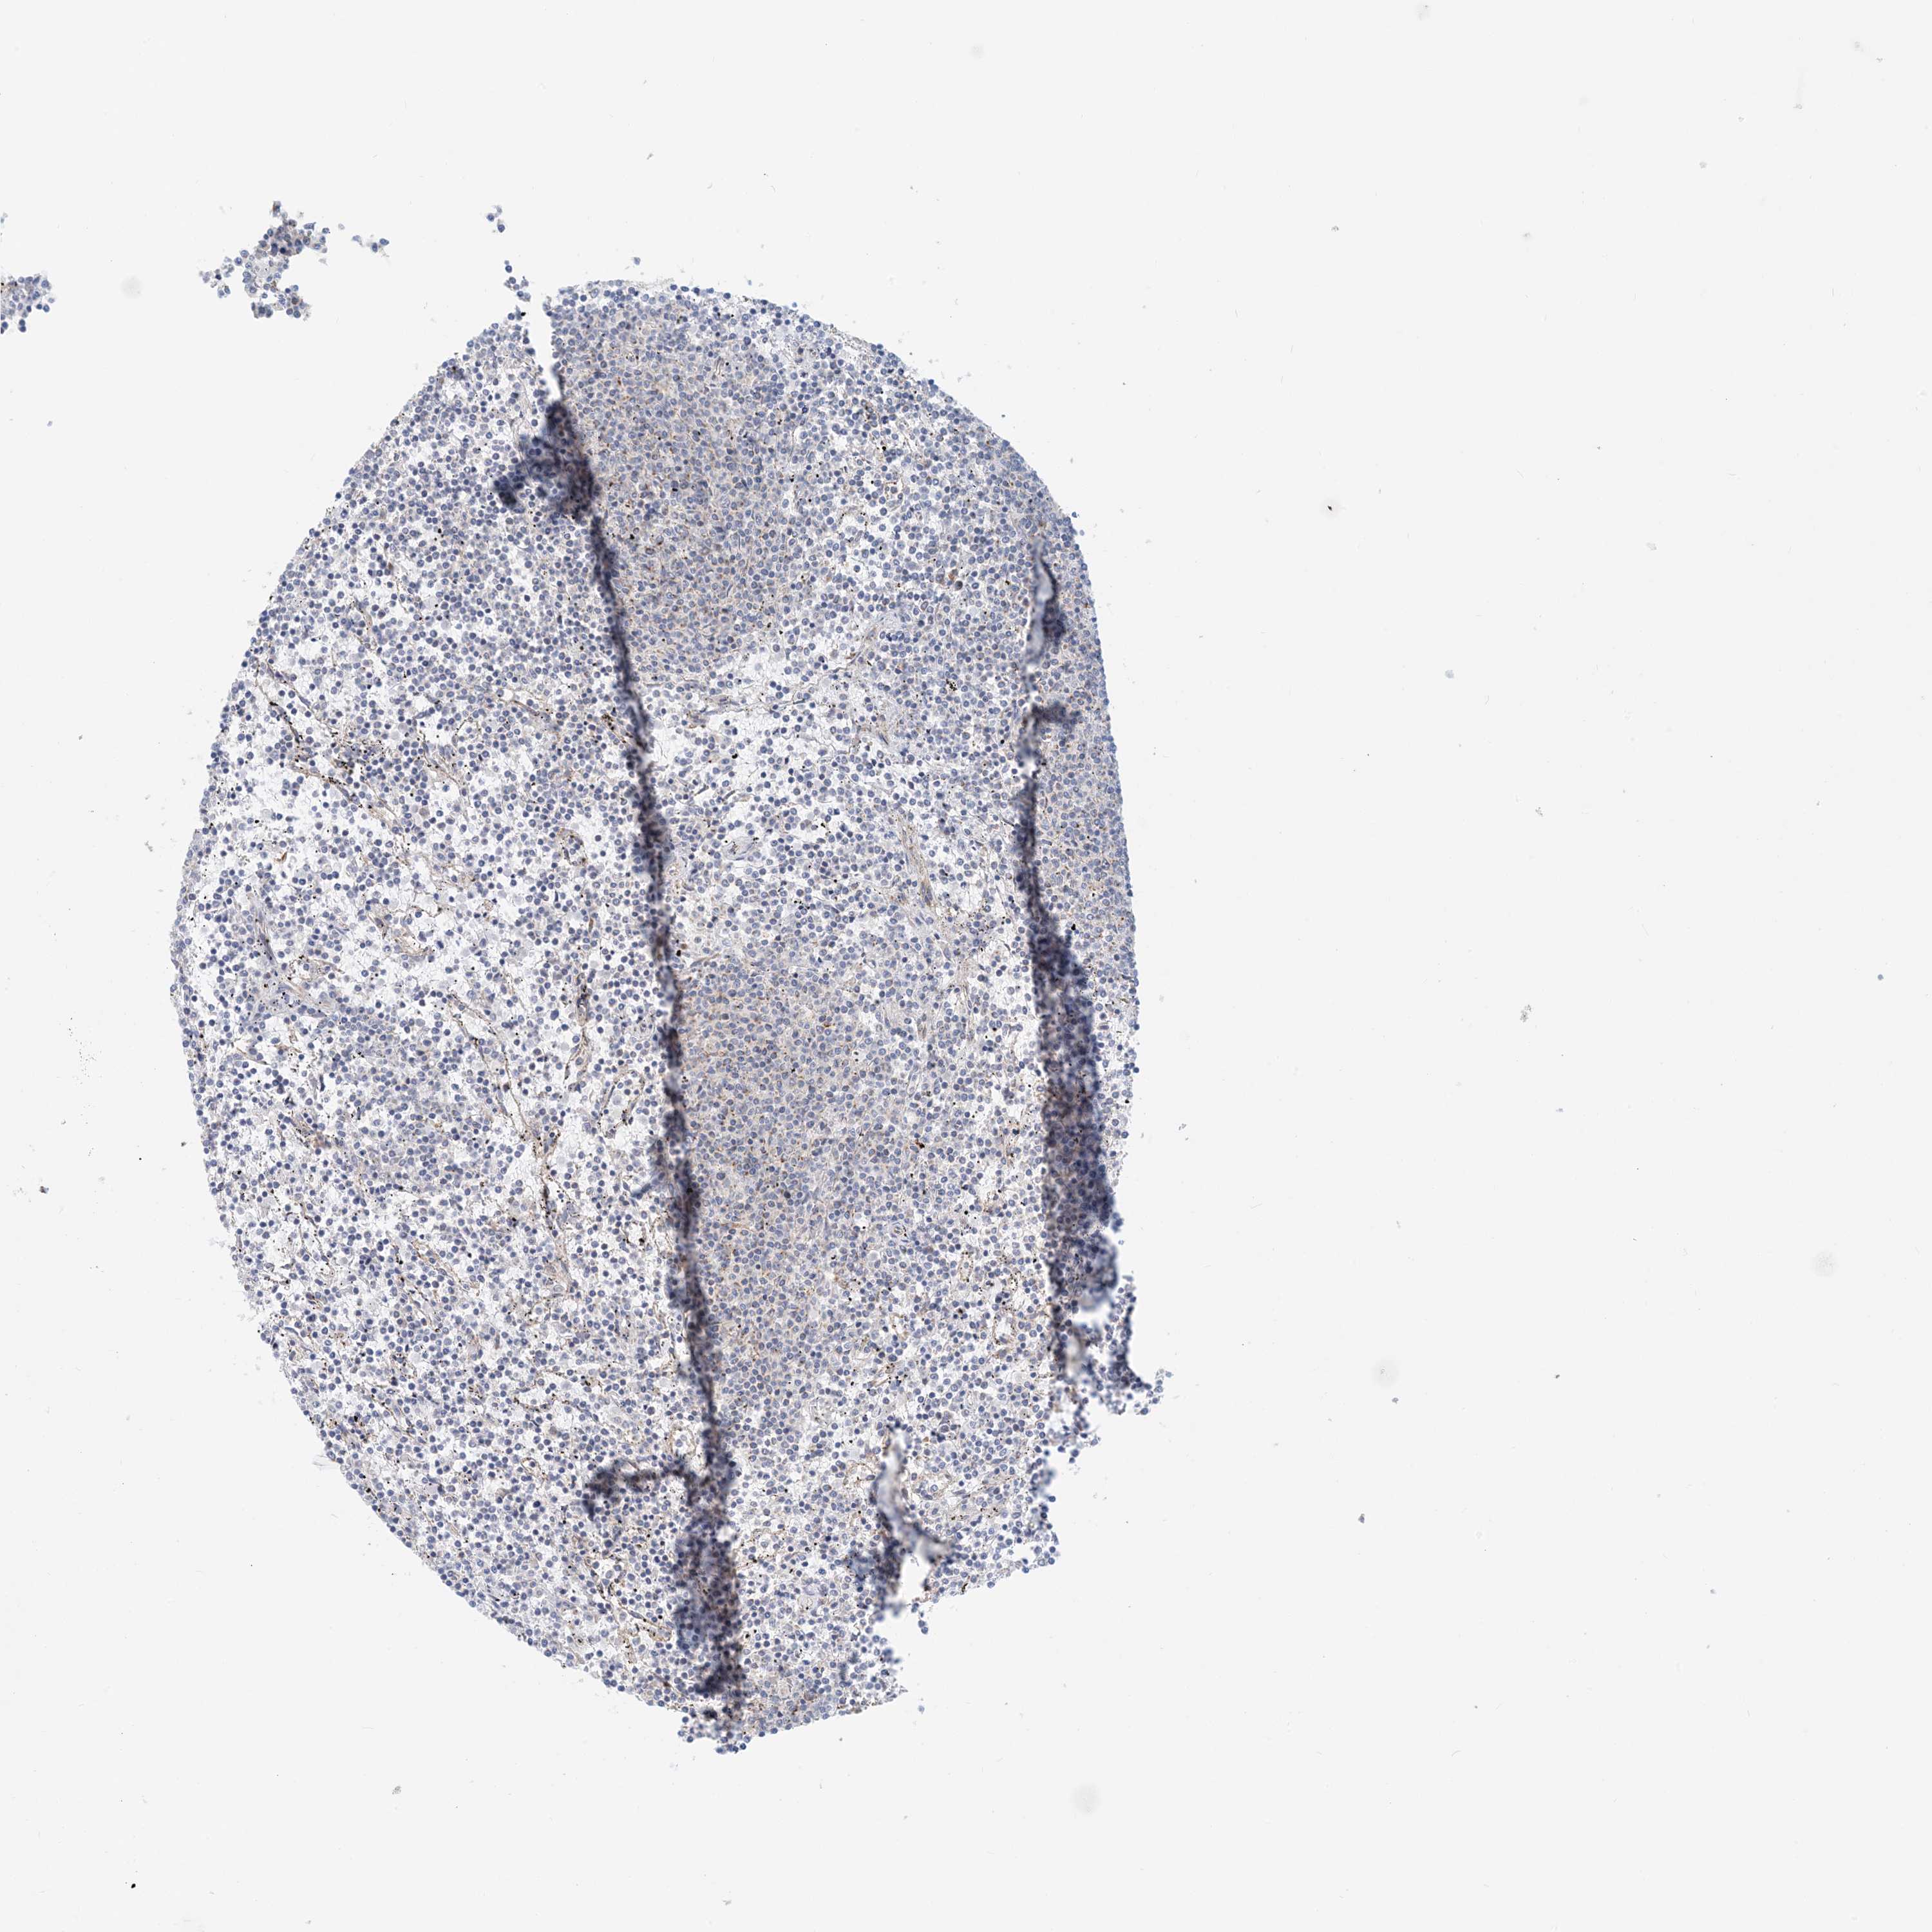

LYMPHOMA - Protein expressioni

A mouse-over function shows sample information and annotation data. Click on an image to view it in a full screen mode. Samples can be filtered based on level of antibody staining by selecting one or several of the following categories: high, medium, low and not detected. The assay and annotation is described here.

Antibody stainingi

Antibody staining in the annotated cell types in the current human tissue is reported as not detected, low, medium, or high, based on conventional immunohistochemistry profiling in selected tissues. This score is based on the combination of the staining intensity and fraction of stained cells.

Each image is clickable and will lead to virtual microscopy that enables deeper exploration of all samples and also displays staining intensity scores, fraction scores and subcellular localization as well as patient and tissue information for each sample.

Antibody HPA031966

Hodgkin's disease, NOS

Malignant lymphoma, non-Hodgkin's type, High grade

Malignant lymphoma, non-Hodgkin's type, Low grade